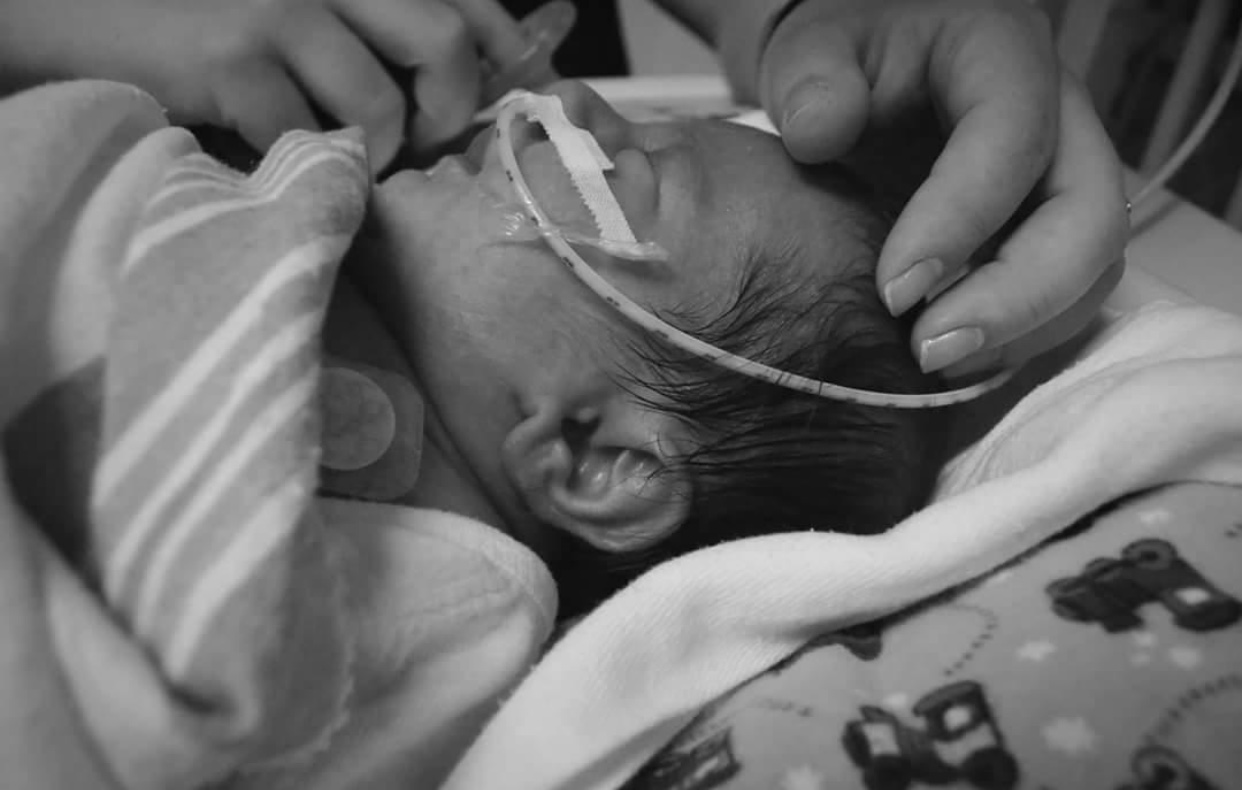

It is with great pleasure, we introduce Oliver Cope as the Celebrity Child for The 62nd Annual Variety Kids Telethon! Oliver was born on March 25th, 2016 and is seven years old.  He lives in Blasdell, N.Y. with his mother (Amanda), father (Eric) and ten year old sister, Frankie!  By just age 2, when many children are littered with bumps and bruises from exploring the world, Oliver had already experienced 31 broken bones. Born with osteogenesis imperfecta (OI), Oliver’s bones are extremely brittle, which causes them to break and fracture easily. Read more below on his resilient spirit and inspiring journey at Oishei Children’s Hospital (OCH) and The Variety Tent #7 Robert Warner, MD Center for Developmental Pediatrics and Rehabilitation.  At Amanda’s 20-week ultrasound, results came back that her baby, Oliver, had a femur that was broken. From there, Amanda had specialist appointments every month until he was born to keep an eye on his development. Doctors were initially confused as to why just his femurs appeared bent and broken. And then they realized his tibias were too short. And then they found that his arms were also underdeveloped. Specialists said it could be either osteogenesis imperfecta (OI), a rare genetic disorder that prevents the body from building strong bones, or dwarfism. Once Oliver was born, it was obvious he had OI. With 8 broken bones, he was in The Children’s Guild Foundation Neonatal Intensive Care Unit at Oishei Children’s Hospital (OCH) for 6 weeks and had 6 more breaks in that time. With Oliver’s condition, he can break a bone by just moving around or being held. Amanda recalls a time when he was just sitting on the couch and moved the wrong way, resulting in a sudden break. Another time, Amanda sat him up and accidentally broke a bone. And yet another time, she was putting him down for bed, scooping underneath him and accidentally broke his collarbone and shoulder blade – it just happens no matter how careful they try to be. Amanda estimates that Oliver has had 11 surgeries so far. His first was at a month old for a feeding tube and then a port for his infusions he was getting every two months, which since then has had to be replaced as it stopped working properly. He has had rods placed in both left and right femurs, tibias and humeri, which were three separate surgeries. The rods in his legs have already been replaced as he grew out of them. In the foreseeable future, Oliver’s arm rods will need to be replaced, but that surgery is down the road for him and his family. Oliver’s condition also causes brittle teeth. He has had caps placed to help protect some of his teeth and 6 other teeth removed as they were worn down. His last set of surgeries were for a new feeding tube along with a colostomy bag. Because his hips tip into the point where they almost touch, Oliver suffers from chronic constipation and a slower digestive system. He is always bloated and backed up, which is somewhat alleviated by his colostomy bag. However, his stoma for the same issue has caused him problems recently. It has prolapsed and herniated, calling for another surgery only a week after being inserted. Once that settled down, it was causing him irritation as it was too close to his skin, resulting in a third surgery. Currently, Oliver participates in physical therapy through The Variety Tent #7 Robert Warner, MD Center for Developmental Pediatrics and Rehabilitation at OCH. Initially fearful of coming and participating in hands-on therapy in fear of breaking a bone, he has grown to trust his physicians and is starting to enjoy his time there. He loves the big walker, working with his therapist and seeing friends that he has made. He is extremely excited to get started with water therapy! Some fun facts about Oliver whose family affectionately calls “Ollie”, include his excitement for building Legos!  He is the #1 fan of Kraft Mac & Cheese and loves the color Red. Sonic, the Hedgehog and Teenage Mutant Ninja Turtles are a few of his favorite things. He is truly a ray of sunshine with a smile that will light up any room.   Variety is thrilled to have Oliver Cope and his loving family a part of The 62nd Annual Variety Kids Telethon taking place Saturday, March 9th from 6pm-11pm on WGRZ, Channel 2 AND on Sunday, March 10th from 10am-8pm on WBBZ, Channel 5 and streaming online.   We hope you will tune in and learn more about Oliver Cope! Please kindly consider making a donation to the Variety Kids Telethon, today!